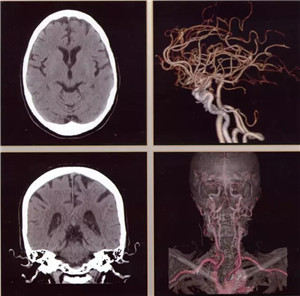

日前,辽阳市中心医院引进当今医学界最先进超高端的美国GE公司生产的Revolution CT(512层)正式投入使用,以此为标志,我市医学影像诊断技术进入超高清时代。该CT是当今世界上临床性能最为强大的CT,它以“合三为一、集大成”的特点引领着CT扫描领域在能谱、速度、宽度方面的国际潮流。落户于中心医院的该CT设备,是东北第三台,辽宁省第二台,目前中国医科大学附属第一医院、盛京医院尚无此种设备。

512层Revolution CT是目前业内探测器最宽、扫描速度超快、射线剂量超低、图像超清晰,且能进行能谱成像的后超高端CT,被称为“革命性”的CT。它实现了——

扫描范围最大:16厘米宽体宝石探测器,心脏、颅脑、肝脏等单器官检查一次扫描就可实现全覆盖;

图像分辨超清:0.23毫米的空间分辨率,对于2毫米冠脉支架的细节和支架内再狭窄清晰可辨;可超早期发现微小肿瘤病变。